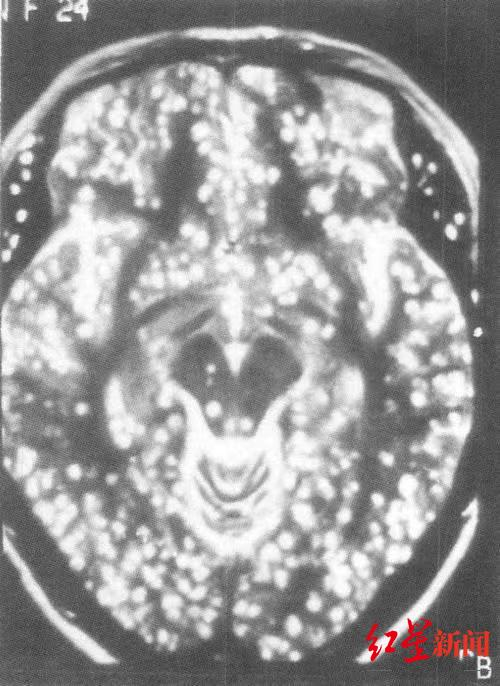

比小胡情况更严重的是今年40岁的张先生,尽管头痛症状才一个月左右,但检查后的影像资料显示,张先生脑中的寄生虫密密麻麻难以计数。“看起来就像一张芝麻饼。”医生这样描述道。

红星新闻记者了解到,张先生常年以来都有吃牦牛干巴,也就是风干的未经过煮熟的牦牛肉的习惯。寄生虫虫卵反复多次进入他的体内,最后脑袋里都长满了寄生虫。